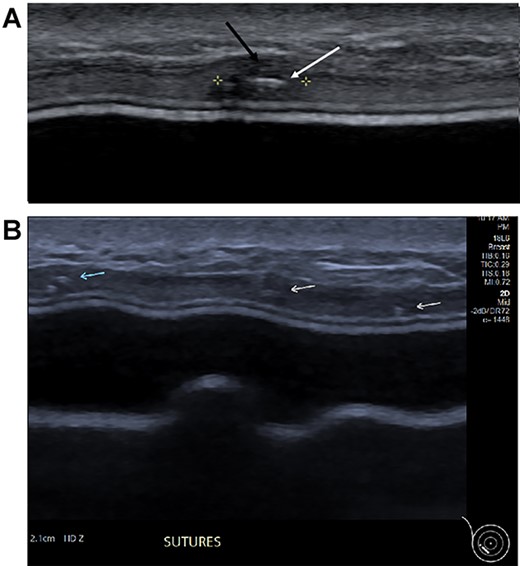

Clinical findings during follow-up were unremarkable until 2020, when she represented with a new lump in the reconstructed left breast neighbouring the mastectomy scar inferiorly. A 1 cm subcutaneous lump with no skin tethering, was palpable along the uniting suture line of the ADM-pectoral muscle. Imaging with ultrasound was indeterminate. This implant proximity rendered it unsuitable for core biopsy due to the high risk of iatrogenic implant perforation (Fig. 2). Subsequent MRI (Fig. 3) illustrated an 11 mm low signal lesion correlating clinically to the palpable lump with mild enhancement but indeterminate appearance.

Ultrasound of the left central breast identified an irregular mass on the capsule of the implant with a focus of hyperechoic calcification (arrow).

(A) Magnified ultrasound image identified a 5 mm hypoechoic focus of thickening within the capsule (black arrow and area between the cursers) with two parallel lines centrally within the focus which represents the suture (white arrow). (B). The ultrasound demonstrates the equally placed sutures identified as small white parallel lines (arrows) across the ADM.